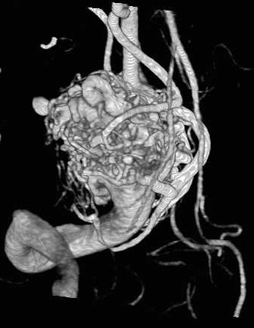

Minden arteriovenosus rendellenességek (AVM) egy tipikus szerkezete:

1.2 - kapott artéria (terminál tranzit és típusa)

3 - a kusza módosított hajók (kernel)

4 - ürítési Bécs

A klasszikus módja, hogy távolítsa el az AVM.